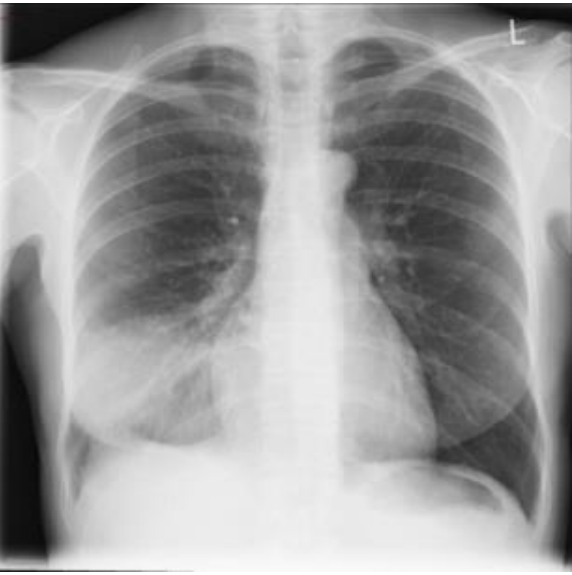

Mulher de 29 anos procura uma Unidade de Pronto Atendimento referindo, há dois dias, febre “alta”, de início súbito, acompanhada de tosse produtiva com expectoração amarelada e leve dor em terço médio de hemitórax direito, na inspiração profunda. Informa ter tido um quadro gripal poucos dias antes. Nega comorbidades, etilismo ou tabagismo. Contudo, relata ter tido um exantema maculopapular, no segundo dia de tratamento com amoxicilina, prescrita para um quadro de angina de evolução arrastada, na adolescência.

Ao exame: bom estado geral, embora abatida e com fácies de doença aguda. Corada, hidratada, anictérica, acianótica, eupneica. Ap Resp: MV universalmente audível, com estertoração crepitante em terço inferior à direita, onde se ausculta broncofonia. ACV, abdome e membros sem alterações. Sinais vitais: FC: 104 bpm; PA: 120/80 mmHg; FR: 20 irpm TAx: 39,0°C. Ao término do exame físico, foi submetida à radiografia de tórax, testes rápidos para Influenza e COVID-19 e coletada amostra de escarro para realização de bacterioscopia pelo método de Gram.

Enunciado 3636306-1

Os resultados evidenciaram:

Testes rápidos: COVID-19 – Negativo. / Influenza – Negativo.

Gram da amostra de escarro: No pequeno aumento, presença de mais de 50 neutrófilos/campo e menos de cinco células epiteliais/campo. No maior aumento (imersão), numerosos diplococos gram-positivos, vários deles intraleucocitários. Raros bastonetes gram-negativos exclusivamente extra-leucocitários.

A conduta terapêutica preconizada para essa paciente é